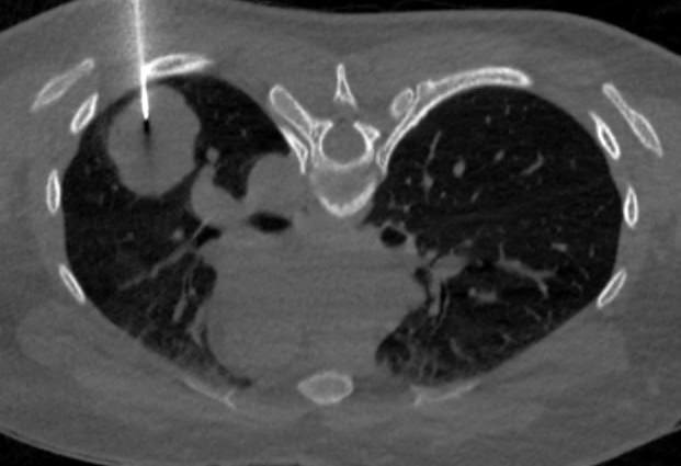

Theo phác đồ điều trị, cứ 21 ngày, bà T. phải truyền thuốc một lần. Riêng thuốc miễn dịch pembrolizumab (Keytruda), mỗi mũi 100ml có giá khoảng hơn 60 triệu đồng. Dù được hỗ trợ theo chương trình “mua 1 tặng 1”, tổng chi phí cho mỗi lần truyền từ 77- 100 triệu đồng do còn nhiều khoản phát sinh như thuốc chống dị ứng, chống nôn, truyền thải độc, vitamin và các xét nghiệm cần thiết. Ngoài ra, cứ 3 tháng bà lại phải chụp CT toàn thân để đánh giá đáp ứng điều trị, làm chi phí tiếp tục đội lên.